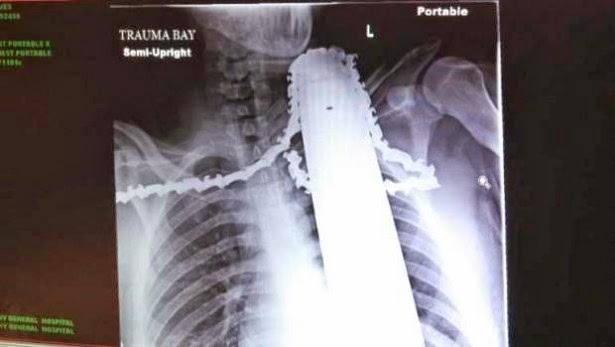

Chainsaw Stuck In Mans Neck

A tree trimmer is recovering after he was rushed to a Pittsburgh hospital with a chainsaw blade embedded in his neckJames Valentine was in a tree in Ross Township on Monday afternoon when he was struck in the neck by the saw.

Another worker helped him down, and his co-workers left the saw in place to try to limit the bleeding. Valentine had emergency surgery at Allegheny General Hospital. Doctors say the saw missed major arteries and instead cut into muscle. The hospital Tuesday released an X-ray showing the saw still in the 21-year-old’s neck.